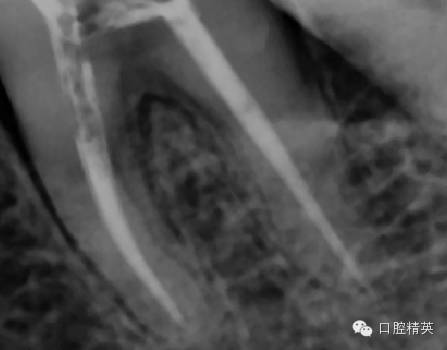

由于近中舌根过于弯曲,所以采用tf镍钛锉预备到30#06锥度,edta,次氯酸钠超声荡洗后,干燥

iroot根充

iroot是生物陶瓷类材料,类似mta,我最喜欢它的固化膨胀效果,根尖封闭效果更好。

tf镍钛锉预备至30#06锥度(虽然根尖区域的预备应该在35#~40#)但我认为这不是根尖周炎,所以仅仅预备到30#,大量次氯酸钠荡洗根管,根充还是用的iroot糊剂和热牙胶,我用的是思博安的热牙胶,很多同行和我说,相比韩国的产品思博安的成本太高了,但思博安的牙胶是 β象限的,低温时的流动性更好,更容易进入狭窄部位和侧支根管,所以我认为,相对与更好的治疗效果,成本并不重要。

近中根管的侧枝清晰可见